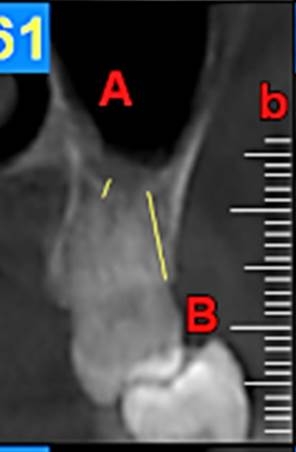

First, the radiographs were evaluated in relation to the endodontic and periodontal problems of the teeth and divided into 5 groups based on periapical index scoring, the periapical status was graded as follows: 1) normal periapical structures; 2) minor changes in bone structure; 3) some changes in bone structure with some loss of minerals; 4) periodontitis with a well-defined radiolucent area; and 5) severe periodontitis with exacerbating features.25 The patients’ genders were also recorded. In the next stage, the teeth were evaluated for the presence of periapical and periodontal lesions, followed by determination of the distance between the maxillary sinus floor and the nearest apex of the root of the first molar (Figure 1, A) and the nearest alveolar crest of the first molar on the buccal or lingual aspect (Figure 1, B). Furthermore, the buccopalatal thickness in the area superior to the apex of the first molar was determined in the coronal dimension (Figure 2). In the next stage, a line was drawn perpendicular to the line connecting the palatal crests of the first molars on both sides in order to measure the depth of the palate (Figure 3). Finally, the thickness of the schneiderian membrane was determined at three regions of the maxilla: medial, lateral and inferior. Then the mean of the 3 values was used as a reference (Figure 4).

Figure 1.A, the distance between the maxillary sinus floor and the nearest apex of the root of the first molar. B, the distance between the nearest alveolar crest of the first molar on the buccal or lingual aspect.